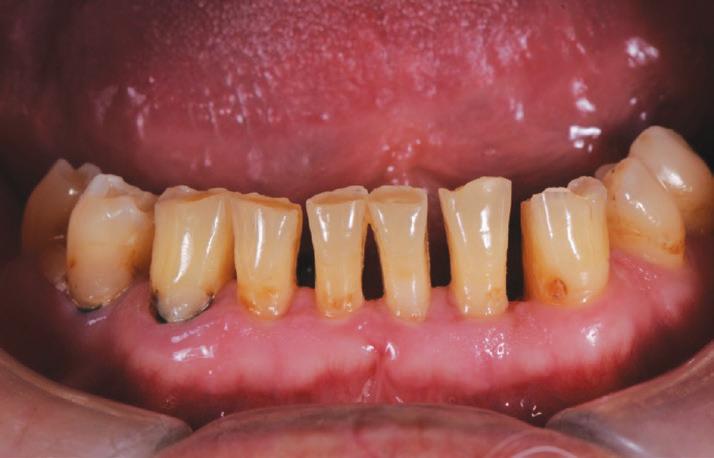

After his examination appointment, it was clear that the two premolars in the upper left quadrant had significant apical pathology and could not be predictably treated. His remaining dentition showed generalised attrition subsequent to dental erosion from gastric reflux, and his lower anteriors showed recession and some loss of periodontal support (Figs. 2, 3).

The teeth were cleaned of plaque and the chipped and unsupported enamel was removed (Figs. 4, 5). Fine bevels were placed to facilitate composite adhesion.

Small, 1/2 round bur undercuts were placed, and all of the exposed

dentine (and the old crown) were micro-etched with the Rondoflex 360 sandblaster, using 27um particles (Figs. 6, 7).